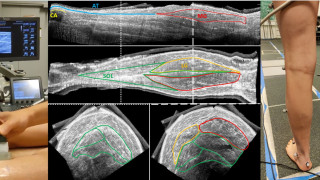

Our main research methods integrate advanced imaging, biomechanical analysis, neuromuscular measurements, and computational modeling:

- 3D ultrasonography and imaging–tracking fusion approaches